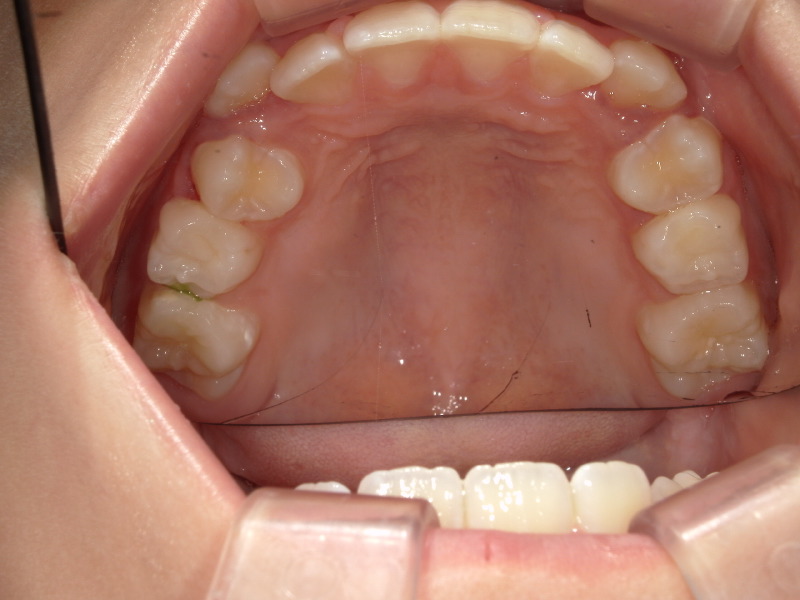

アクティビティー卒業後

経過観察中

アクティビティーが終わっても永久歯列になるまでは数ヶ月に一度のご来院をお願いしています。

歯並びも順調に生え変わりましたが、左側の後ろから2番目の歯は少し歪んだ方向から生えてきました。

患者さん自身は今は気になっていないため、一旦治療は終了していますが、希望があればマイオブレース(myobrace)治療にて改善も可能です。